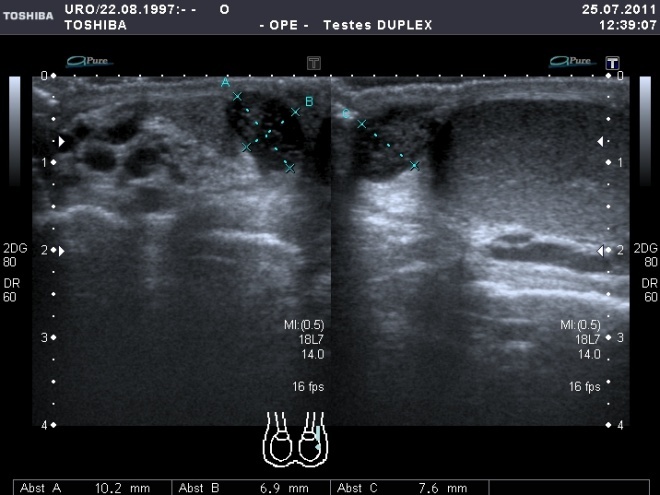

Duplexsonographisch eindrücklich ist bei einer Hodentorsion das völlige Fehlen des intratestikulären Blutflusses. Durch den komplett unterbundenen venösen Abfluss treten ödematöse Veränderungen im Hodenparenchym auf (interstitielles Ödem). Der betroffene Hoden imponiert echoärmer und größer, und es bildet sich häufig eine Begleithydrozele aus.

Im Falle einer länger bestehenden Hodentorsion sind Gewebeinfarzierungen zu beobachten und das Hodengewebe beginnt sich mit einsetzender Lyse zystisch umzustrukturieren. Auch im Rahmen dessen findet sich eine nachweisliche Hydrozelenbildung. Zurück bleibt dann letztendlich ein sog. atrophes Hoden-Nubin.